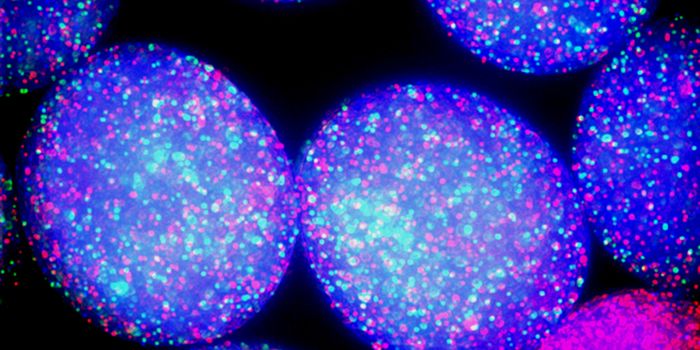

AUG 11, 2016Cell & Molecular BiologyIn new research published in the journal Angewandte Chemie, scientists applied a high throughput methodology to study th ...